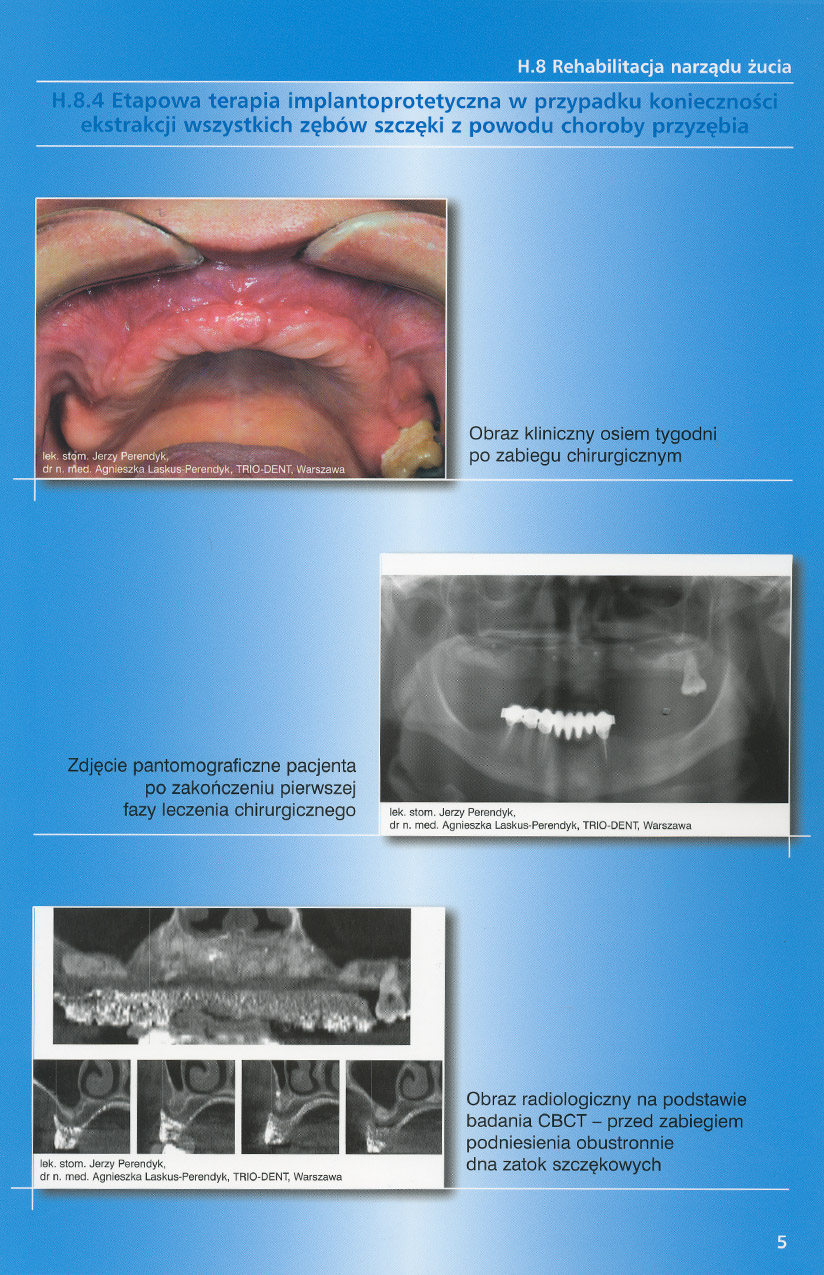

zobacz więcejGaleria przypadków klinicznych, obrazująca proces terapeutyczny od stanu wyjściowego aż do oddania ostatecznej pracy uzupełnienia brakującego uzębienia.